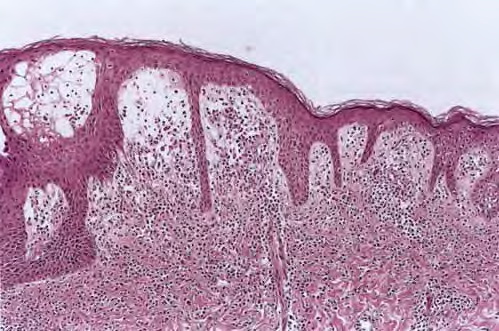

Branchial cleft cyst =كيسة الشق الغلصمي Branchial Cyst (Branchial Cleft Cyst) Sequestration of first or second branchial cleft membranes results in these cysts, sinuses, or tags. EPIDEMIOLOGY Branchial cleft cysts are largely sporadic, but autosomal dominant cases have been reported. There is no gender predominance. Ten percent of lesions are bilateral. ETIOLOGY AND […]